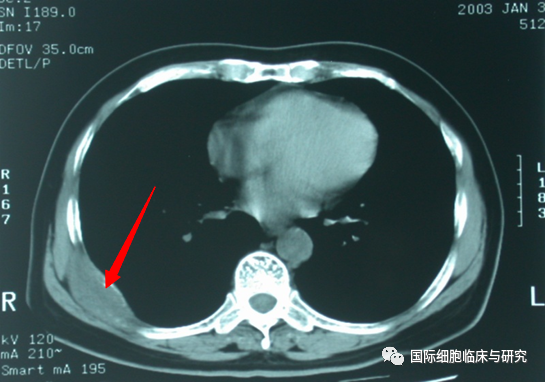

门静脉癌栓

下腔静脉癌栓